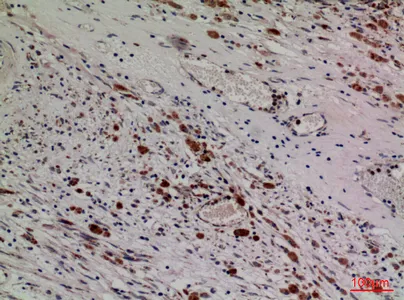

MPO Rabbit Polyclonal Antibody

Cat: APRab14056

Size1:50μl Price1:$118

Size2:100μl Price2:$220

Size3:500μl Price3:$980